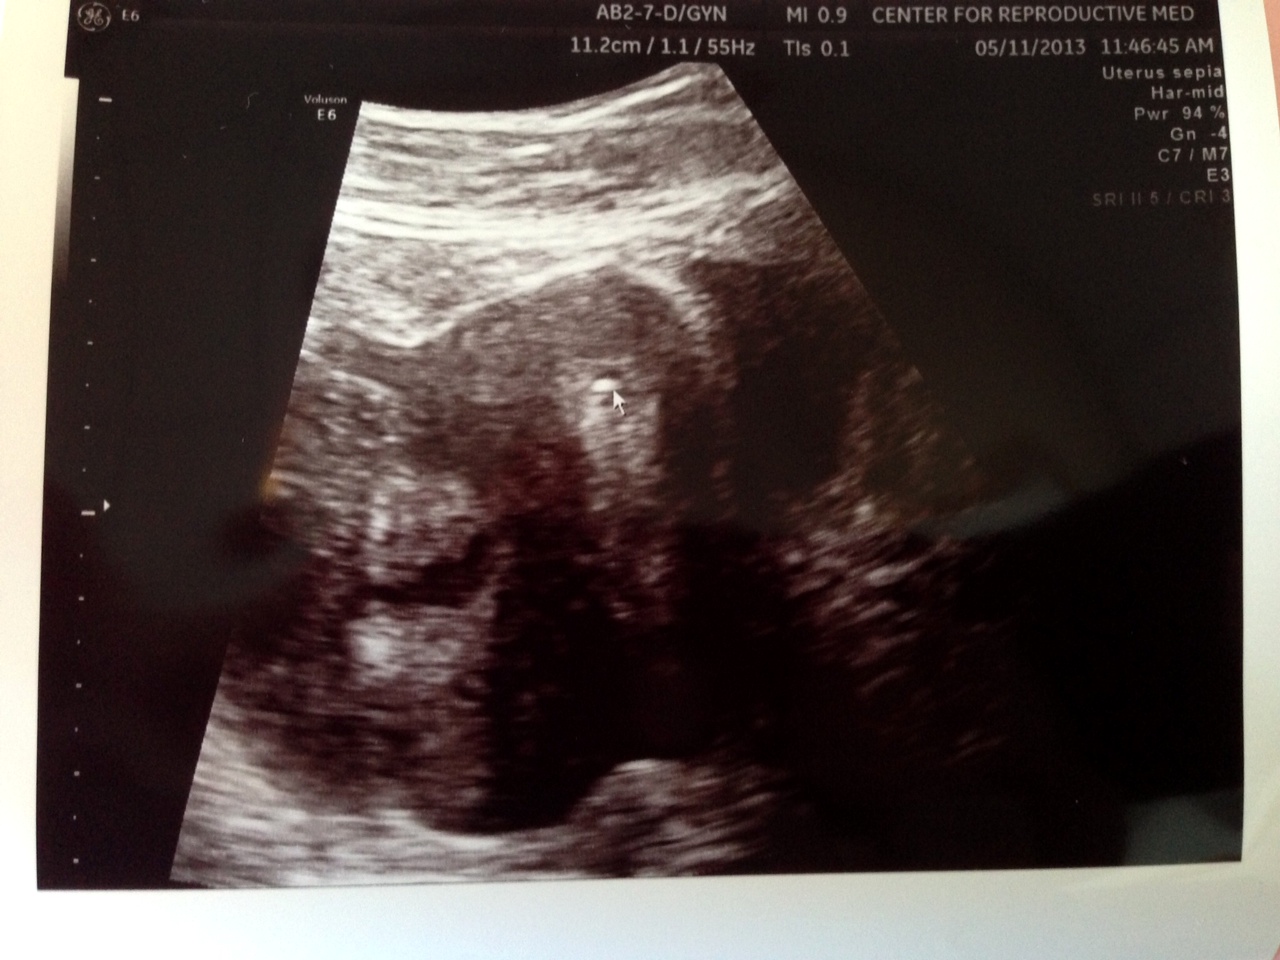

Now – on to happier things! Josh and I are doing really well. I feel really grateful that we have been surrounded with so much support and love as we dealt with the reality of our BFN (big fat negative.) We are excited to be moving forward with our FET (frozen embryo transfer). We meet with our nurse consultant next Wednesday to get our final prescriptions, sign and sign and sign some papers, and finalize the cycle. I have so much to more to share about a great conversation with our doctor and answer many of the questions that you guys have been asking me about “why is this happening?” and “what are your chances now?”. I will save that for another post in the next couple days – as well as fill you in on my first fertility acupuncture appointment. (Funny story, I promise.)